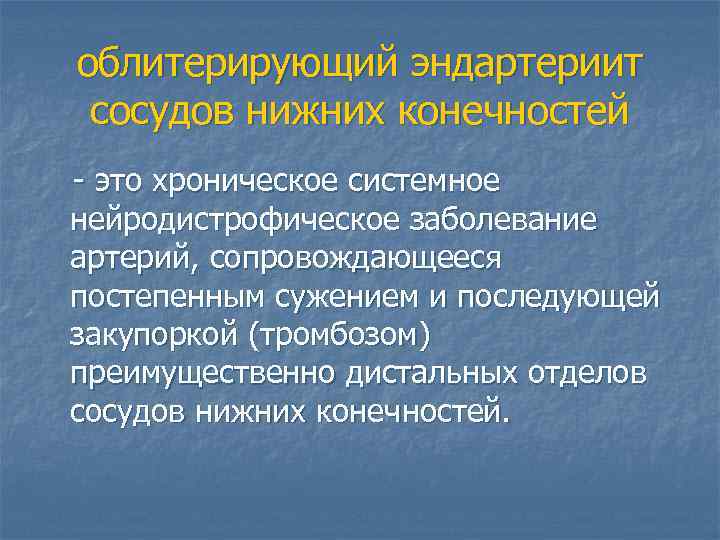

облитерирующий эндартериит сосудов нижних конечностей - это хроническое системное нейродистрофическое заболевание артерий, сопровождающееся постепенным сужением и последующей закупоркой (тромбозом) преимущественно дистальных отделов сосудов нижних конечностей.